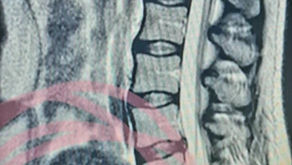

In 2017 had ik zo’n moment. Ik kreeg de diagnose Multiple Scleroses die een minder florissante prognose heeft. ‘Zorg goed voor je zelf en geniet van het leven’ was het advies. Dat is dan ook wat ik ben gaan doen. Het leven met een chronische diagnose is op zijn zachtst gezegd een uitdaging. Echter, het is nog steeds mijn leven dat centraal staat en niet mijn ziekte.